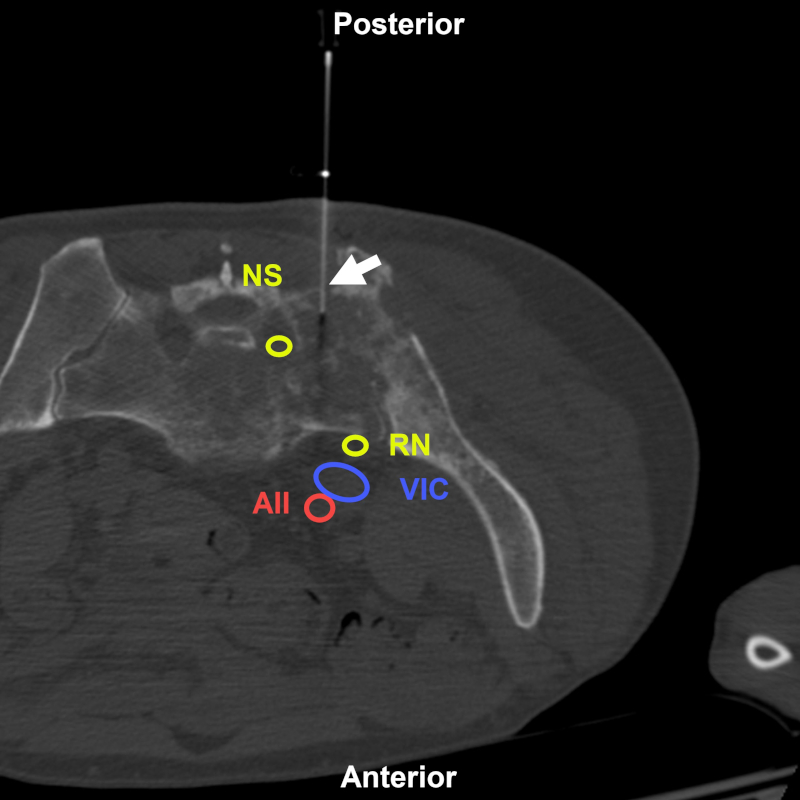

Varón de 73 años en estudio por lesión lítica sacroilíaca izquierda. BP con abordaje directo posterior (flecha) bajo TC. Estructuras a evitar: NS: nervio sacro; RN: raíz nerviosa de L5; VIC: vena ilíaca común; AII: arteria ilíaca interna. Aguja utilizada: Franseen 20 G. Diagnóstico final: infiltración por carcinoma de pulmón.

Figura 14